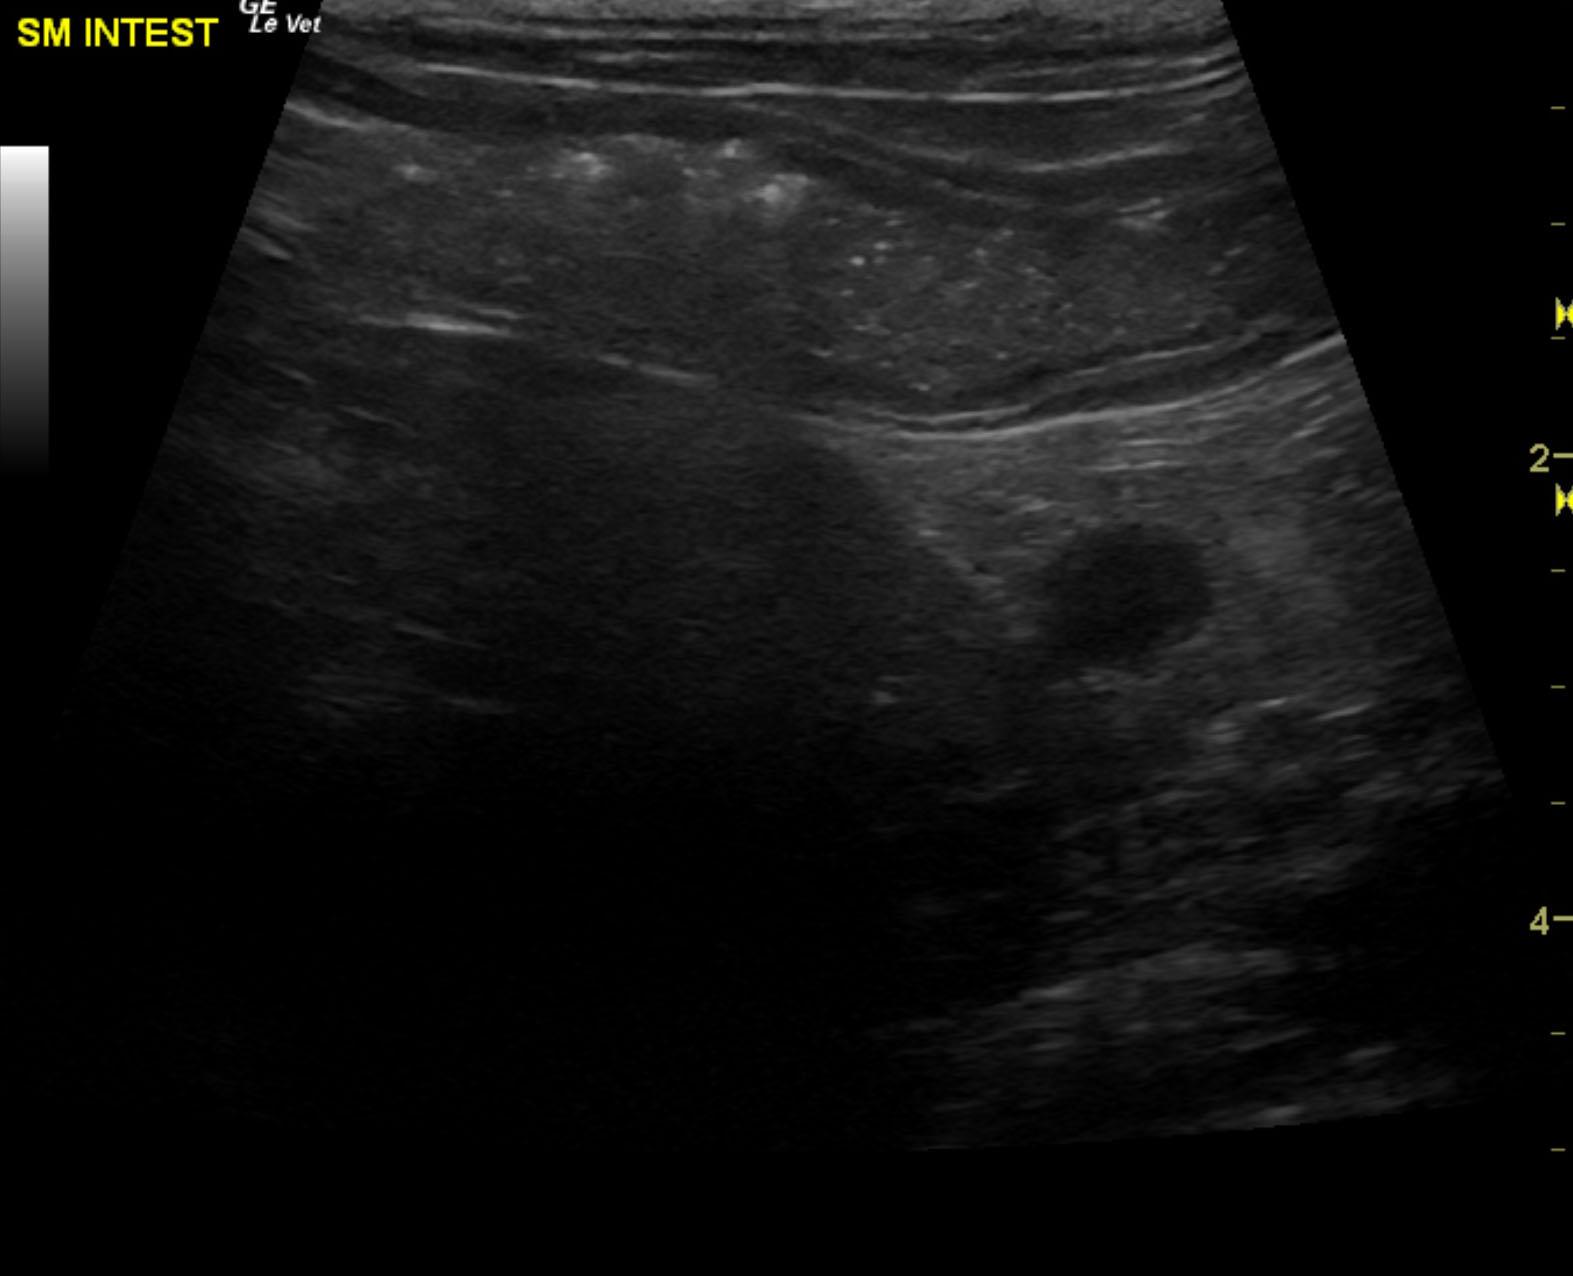

The patient is a 13 year old spayed female Dachshund dog which was presented for four days of anorexia and vomiting. She was given Cerenia, which helped, but still had ileus. Dog has vomited carpet material in past. Spec cPL was normal. Radiographs revealed dilated intestine, which appeared to be colon and cecum.